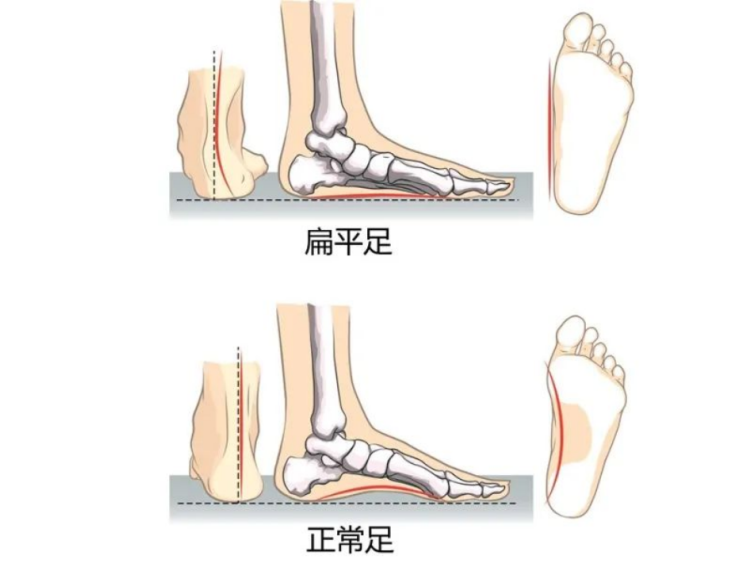

正常脚底内侧有一个拱形,从脚跟一直延伸到大脚趾的底部,我们称之为足弓。当脚没有足弓时,称为扁平足或平足。扁平足是常见的青少年临床问题之一,主要表现为足跟外翻,足内侧弓塌陷,前足外展,整个脚底负重,该病症患者负重力线不正常,发展到一定程度可出现足部疲劳或疼痛症状,从而出现不能长时间的站立和行走、奔跑和运动表现差的情况。

对于很多家长来说,可能仅仅知道平足是外形上的畸形。平足可以是无痛的,但如果畸形明显,可能会存在疼痛。如果青少年扁平足长期没有得到矫正或治疗,畸形继续发展,会导致行走不稳,容易摔跤,体育运动可能较正常孩子要差,甚至会出现肌腱疲劳变性、韧带撕裂、关节软骨磨损,继发骨性关节炎的改变,以及影响踝、膝、髋关节、腰椎功能。